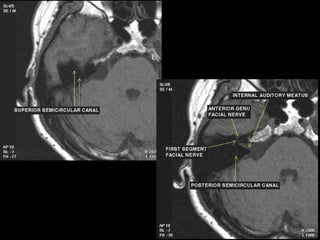

Segments

 intracranial (cisternal) segment - zero branches

 meatal (canalicular) segment (internal auditory canal): 8 mm long, zero branches

 labyrinthine segment (IAC to geniculate ganglion): 3-4 mm long, 3 branches

(from geniculate ganglion)

 tympanic segment (from geniculate ganglion to pyramidal eminence): 8-11 mm

long, zero branches

 mastoid segment (from pyramidal eminence to stylomastoid foramen): 8-14 mm long, 3

branches

 extratemporal segment (from stylomastoid foramen to division into major branches): 15-

20 mm, 9 branches